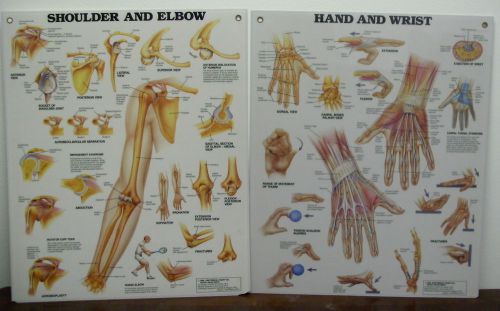

Lot of 2 Laminated Anatomical Wall Charts " Shoulder & Elbow"and "Hand & Wrist"